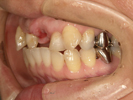

50代女性

治療前 |

治療中。仮歯。 左上の奥にインプラント埋入。 噛みあわせ治療を行いました |

治療後 全体の歯で食事がおいしくできるようになったと喜んでおられました。 |